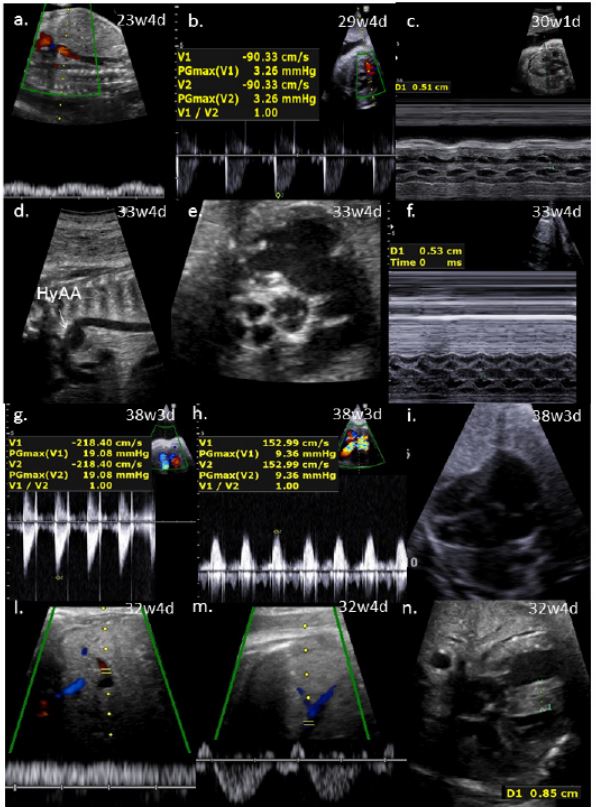

Figure 1: Prenatal ultrasound findings in the 4 fetuses with NS.

Case 1 a: Ductus venosus was not detectable. b. Doppler velocity in the main pulmonary artery was at the top of the normal range. c. Interventricular septum was thickened.

Case 2 d: Hypoplasia of aortic arch (HyAA). e. Semilunar valves were thickened and pulmonary valve (PA) seemed to be bicuspid. f. Interventricular septum was thickened.

Case 3: g.h. Doppler velocity was increased in both pulmonary artery and aorta because of the obstruction of the outlets. i. Redundant foramen ovale flap.

Case 4 l.m. Umbilical and sovrahepatic veins. Ductus venosus was not detectable. n. Interventricular septum was thickened.